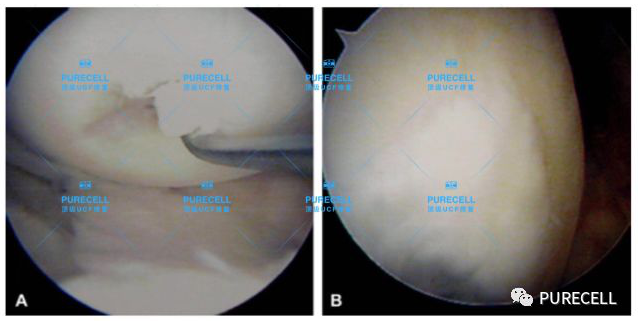

PURECELL首席科學家以及運動醫療專家已經驗證了UCF對膝關節修復的有效性,下圖是UCF軟骨及半月板修復前後影像對比。

UCF膝關節修復的主要原理是通過UCF成分,改善膝關節內環境,有效激活幹細胞靶向修復膝關節組織,修復韌帶損傷、半月板損傷,修復軟骨及髕骨等組織,能有效減少軟骨受損、骨刺等所帶來的疼痛,並且有效避免了軟骨半月板等膝關節組織的持續磨損和惡化,從根源上改善膝關節疼痛等問題給生活帶來的困擾。

1573813016CUCu9B3I.png

1573813038XEa64cgj.png